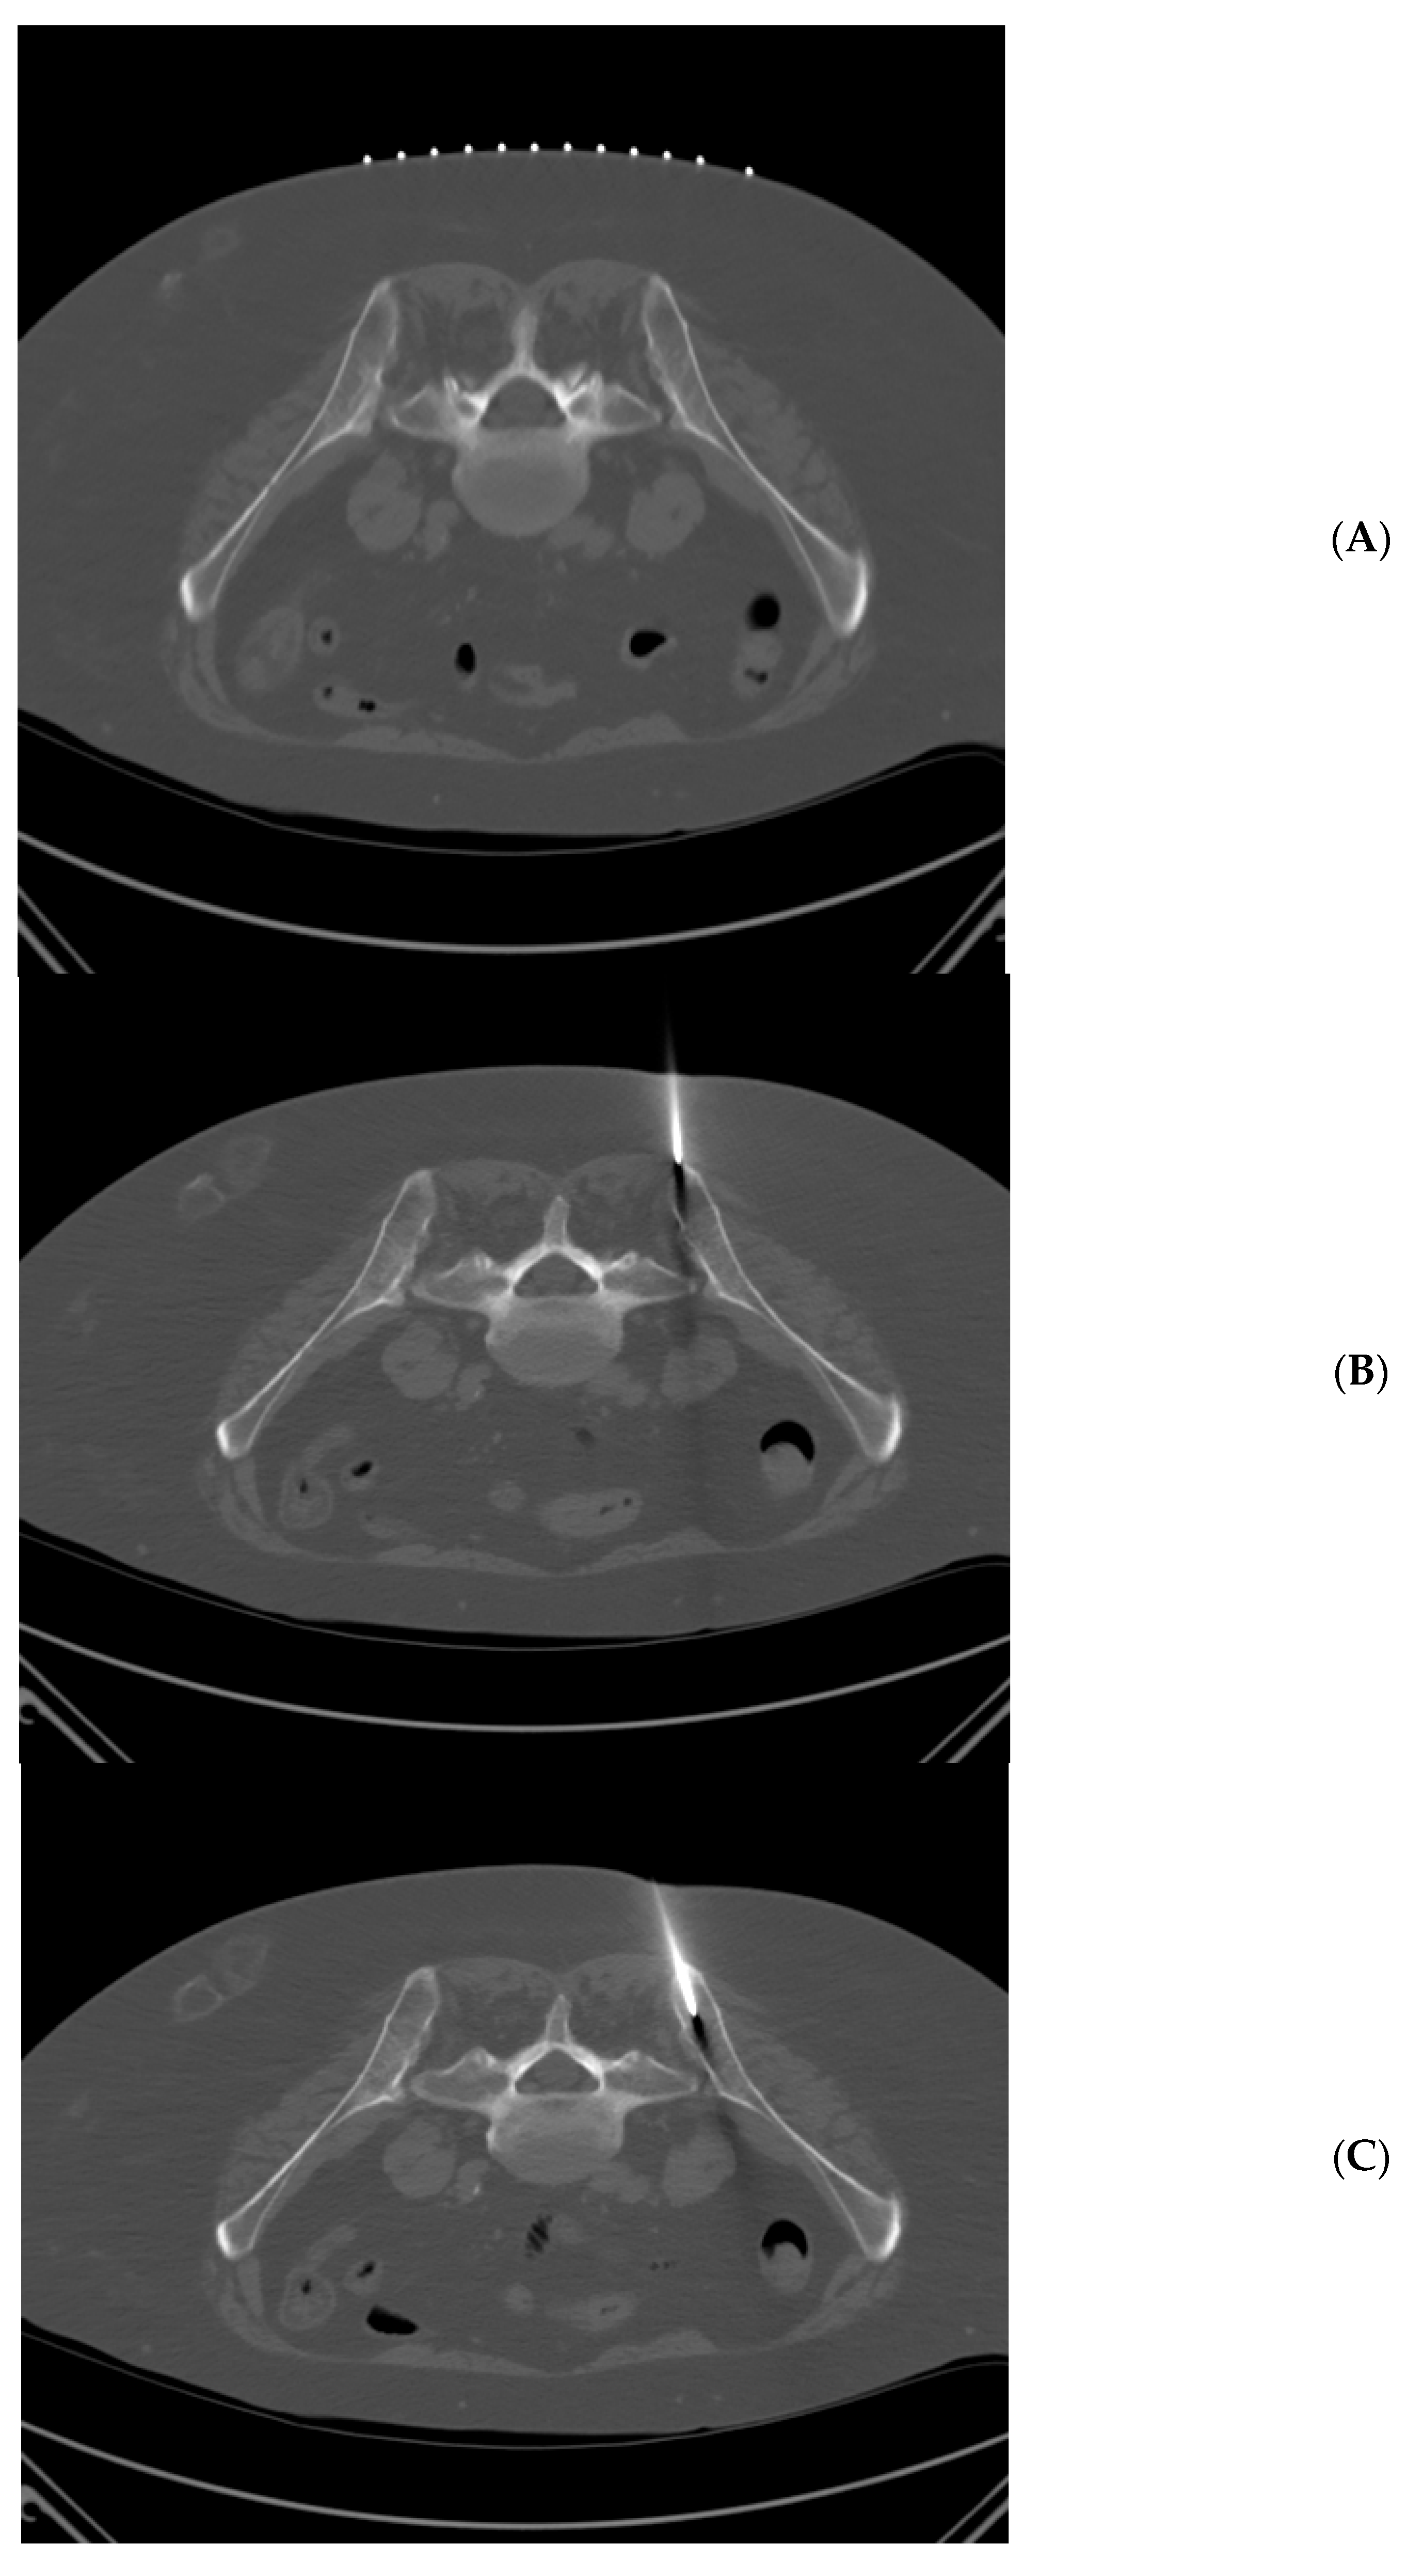

Figure 1.

71 year-old woman with acute myeloid leukemia. Technically successful biopsy, but insufficient pathologic diagnosis. (A) Prone position pre-planning CT with skin guidance markers on the right side of the patient. (B) Prone position CT with biopsy needle tip approaching right posterior iliac spine. (C) Prone position CT with biopsy needle tip within the right posterior iliac spine.